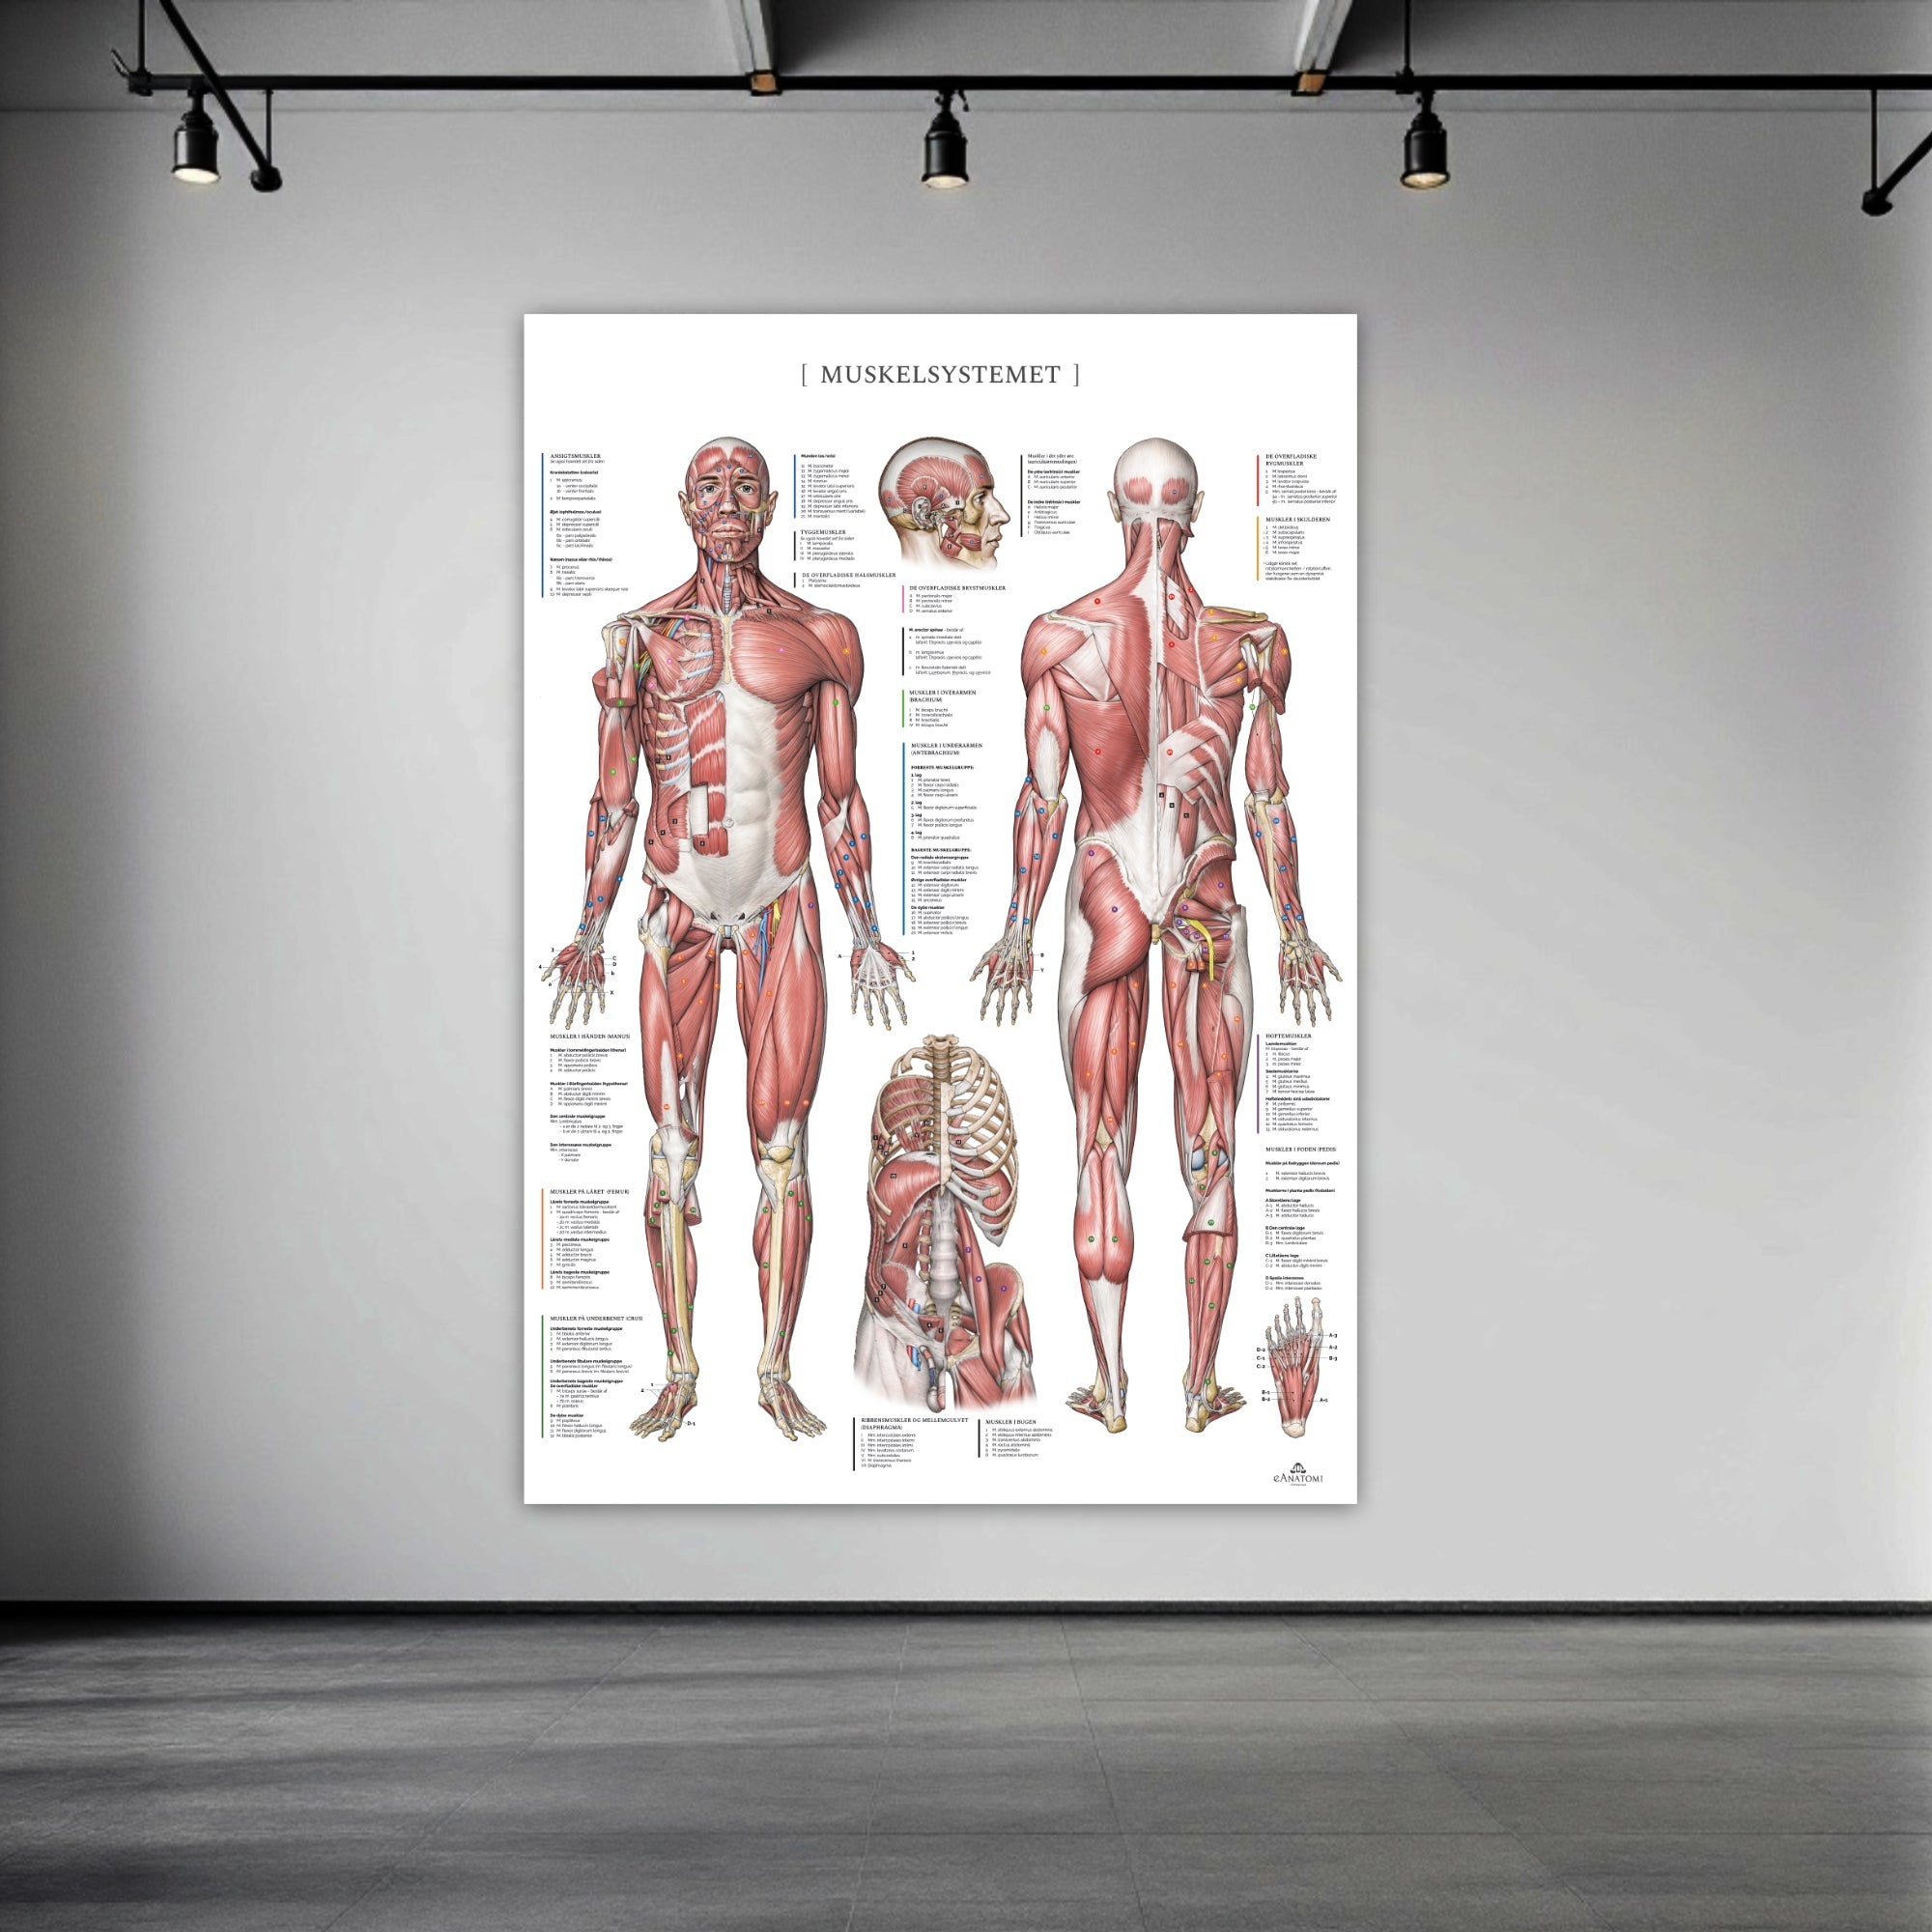

Vores anatomiske varesortiment